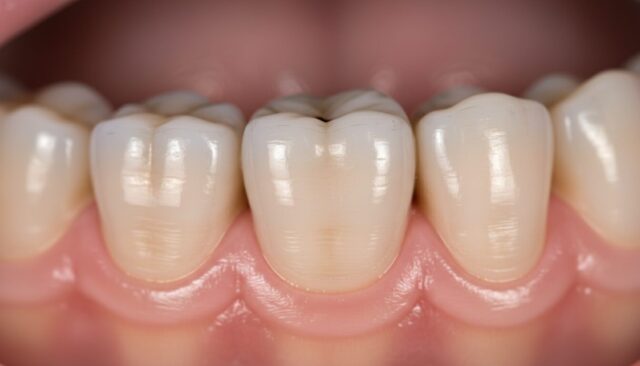

正常に生えて機能している場合

親知らずが上下で正常に生えて噛み合っている場合、特に抜く必要はありません。手前の歯と同じように生えていて、歯磨きも問題なくできる状態であれば、そのまま残しておくことができます。

正常に機能している親知らずは、将来的に手前の歯が抜けてしまった場合にブリッジの土台や移植歯として使える可能性があります。